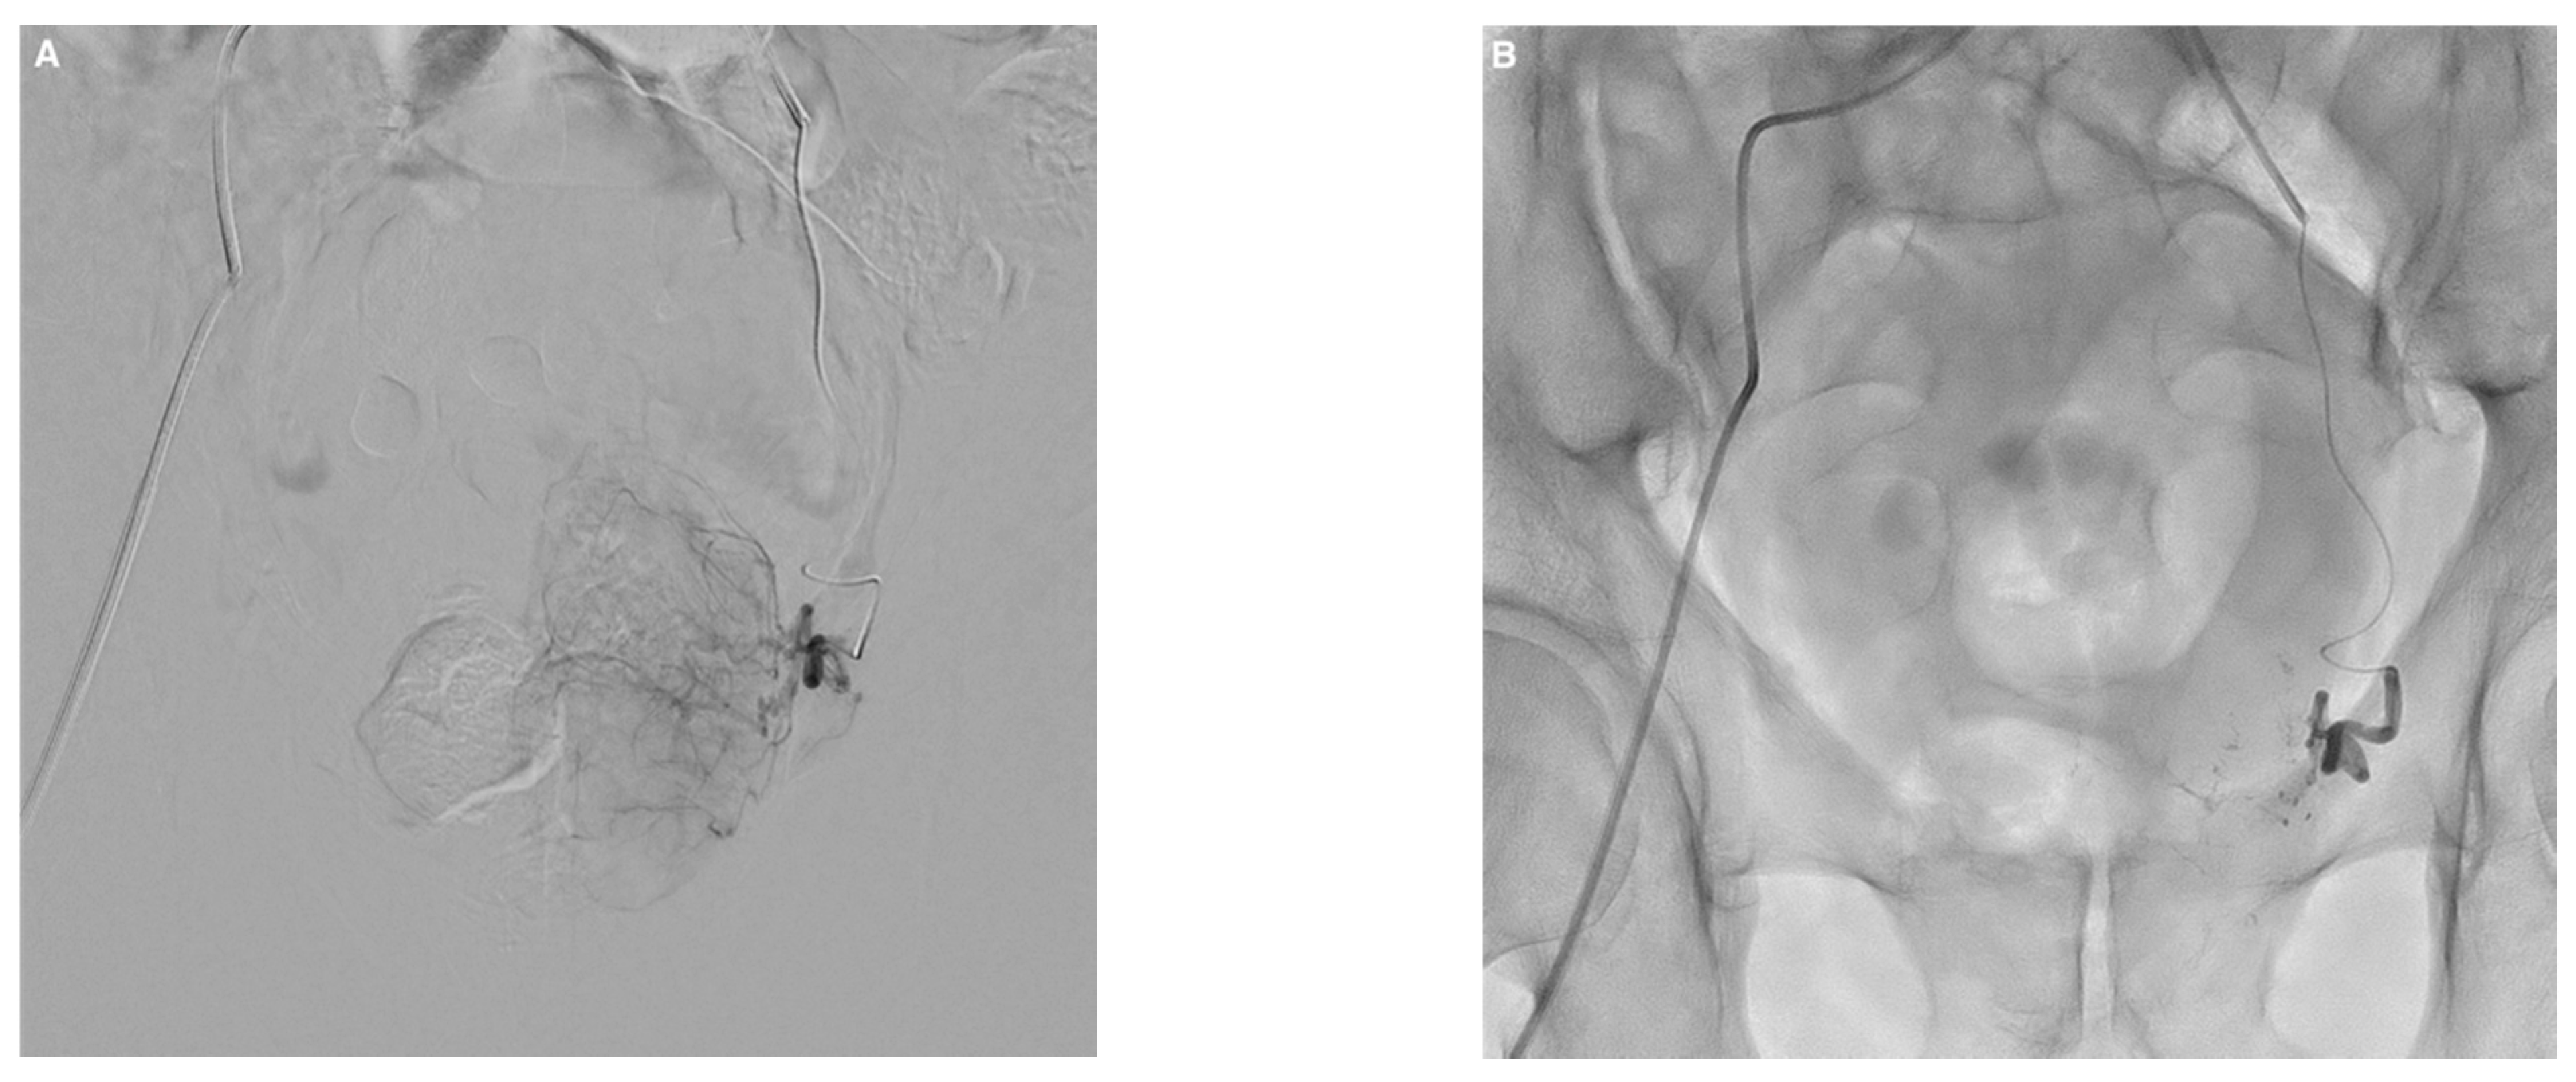

Embolization was performed according to established techniques, bilaterally in most cases (Figure 1) []. After microcatheter positioning within the feeding artery, 2 mg of isosorbide dinitrate (Risordan, 10 mg/10 mL vial) was administered intra-arterially on each side for vasodilation. The microcatheter dead space and vascular bed of the prostatic lobe were then abundantly flushed with 10 mL of 5% dextrose solution to prevent polymerization and promote distal embolization. NBCA glue (Glubran 2, GEM; Viareggio, Italy) was diluted with iodized oil (Lipiodol Ultra Fluid; Guerbet, Aulnay-sous-Bois, France) to make the material radiopaque. A homogeneous NBCA–Lipiodol mixture was prepared immediately before the injection using two 5 mL luer-lock syringes and a three-way stopcock. A high NBCA dilution of 1:8 was used to increase mixture fluidity, thereby allowing distal embolization. Embolization was performed in free or blocked flow. Effectiveness was assessed visually during PAE, and the injection was stopped when substantial reflux occurred. The microcatheter was then promptly removed.

Figure 1.

Example of prostate artery embolization (PAE) with N-butyl cyanoacrylate glue in a 74-year-old patient with symptomatic benign prostatic hyperplasia. (A) Left prostatic artery angiogram before PAE showing enhancement of the left prostatic lobe. (B) Follow-up angiogram after PAE with a mixture of Glubran®2/Lipiodol in a 1:8 ratio showing total occlusion. (C) Right prostatic artery angiogram with enhancement of the right prostatic lobe. (D) Visualization of the glue/lipiodol cast in the branches of the right prostatic artery after injection of the same mixture, with complete occlusion. (E,F) Axial cone-beam computed tomography images without contrast injection after bilateral PAE showing lipiodol uptake by both prostatic lobes with distal and proximal distribution of the glue/lipiodol casts. Major improvements in lower urinary tract symptoms were noted 3 months after PAE compared to baseline (IPSS, 5 versus 24; QoL score, 2 versus 6; prostate volume, 110 versus 170 mL).